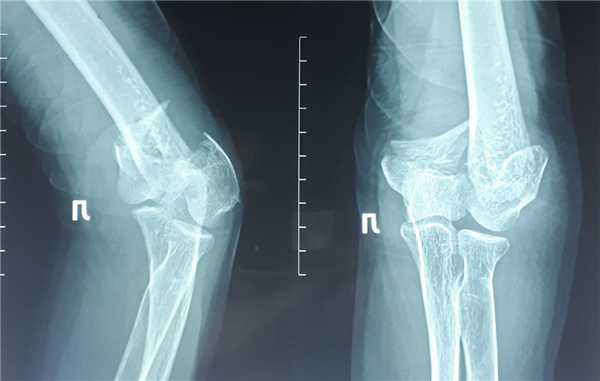

На представленных ниже рентгенограммах локтевого сустава определяется оскольчатый перелом мыщелков левого плеча с 4 большими фрагментами.